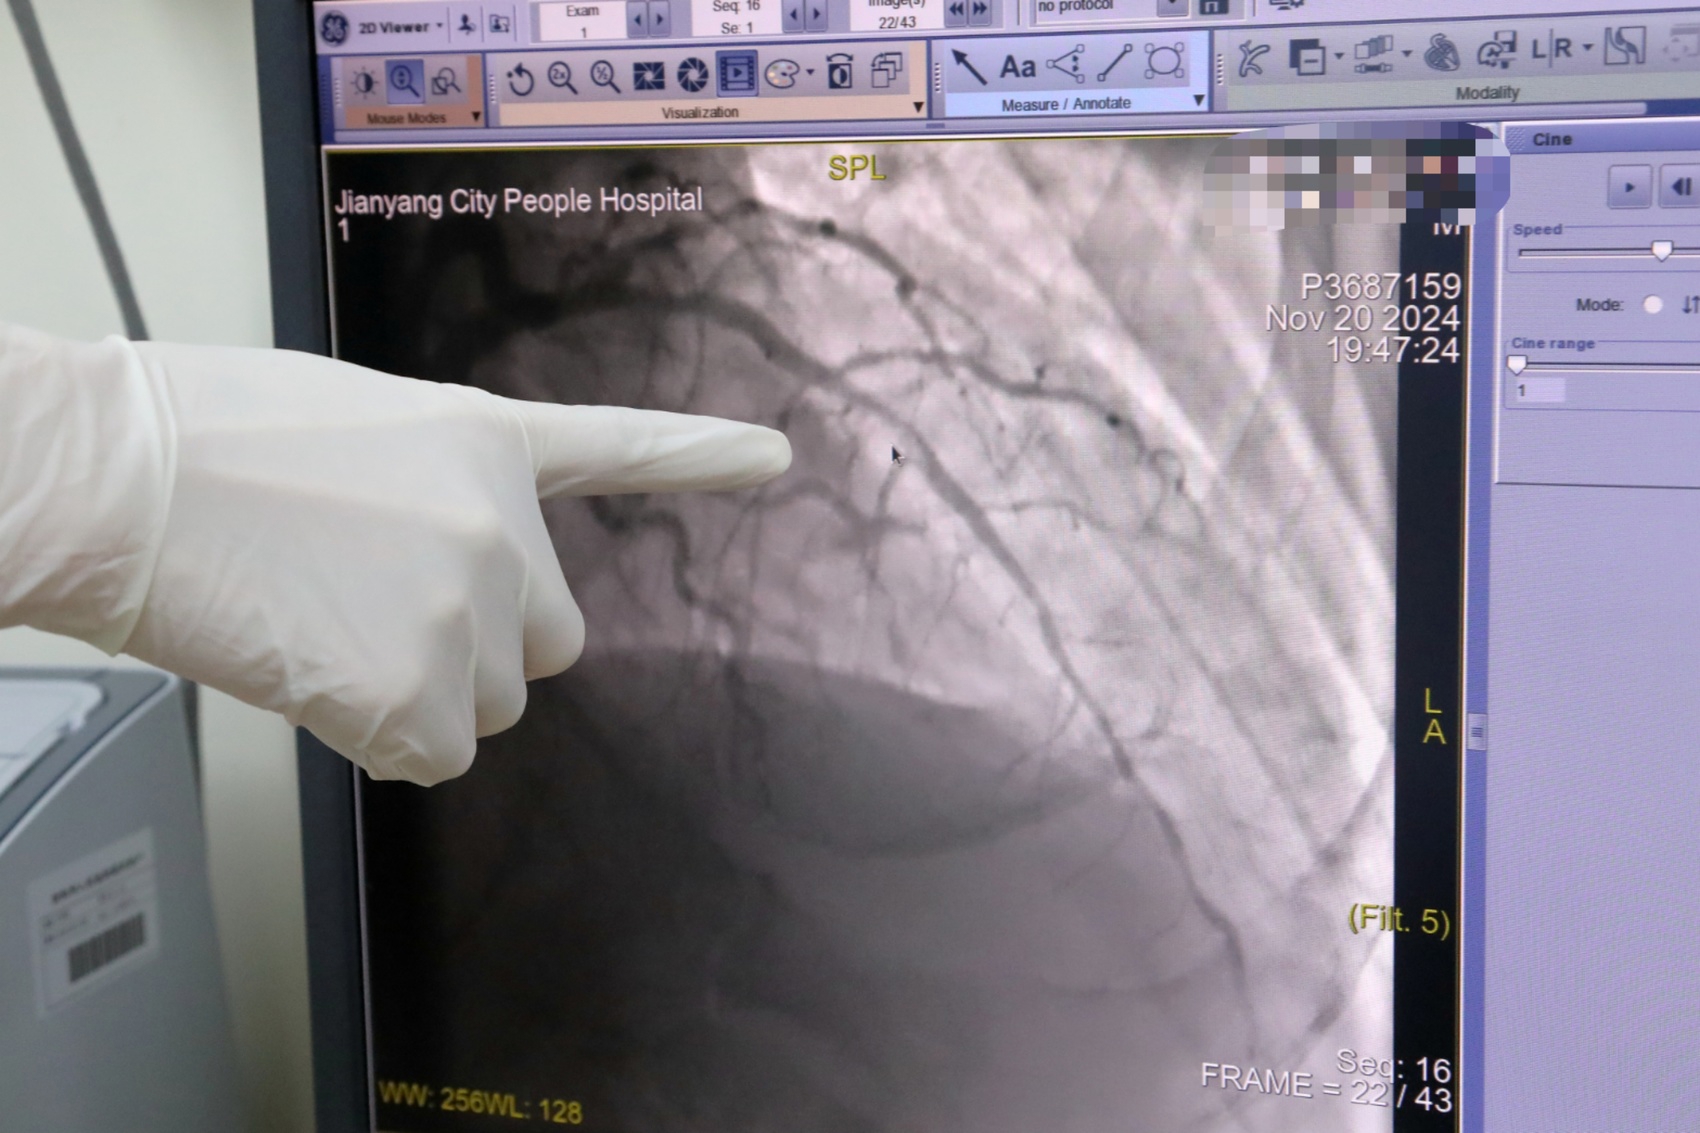

20多分钟后,患者被送达医院,立即复查心电图,明确诊断为“急性前壁ST段抬高型心肌梗死”。这种病情最好的解决办法就是尽快手术开通闭塞的冠状动脉,以挽救濒死的心肌。在得到患者及家属的同意后,主刀医生罗智立即展开手术,患者胸痛的症状逐渐缓解,生命体征逐渐恢复正常。由于患者冠脉血管病变严重,术中通过血管内超声发现严重的钙化,以及多处的弥漫性病变,本次手术成功后仍然需要择期接受二次手术治疗,以进一步改善冠脉供血,降低再次发病的风险。患者术后患者恢复良好,4天后顺利出院,患者及家属对所有参与抢救的医护人员表达了衷心感谢。

术后患者闭塞的血管恢复供血 胡波摄